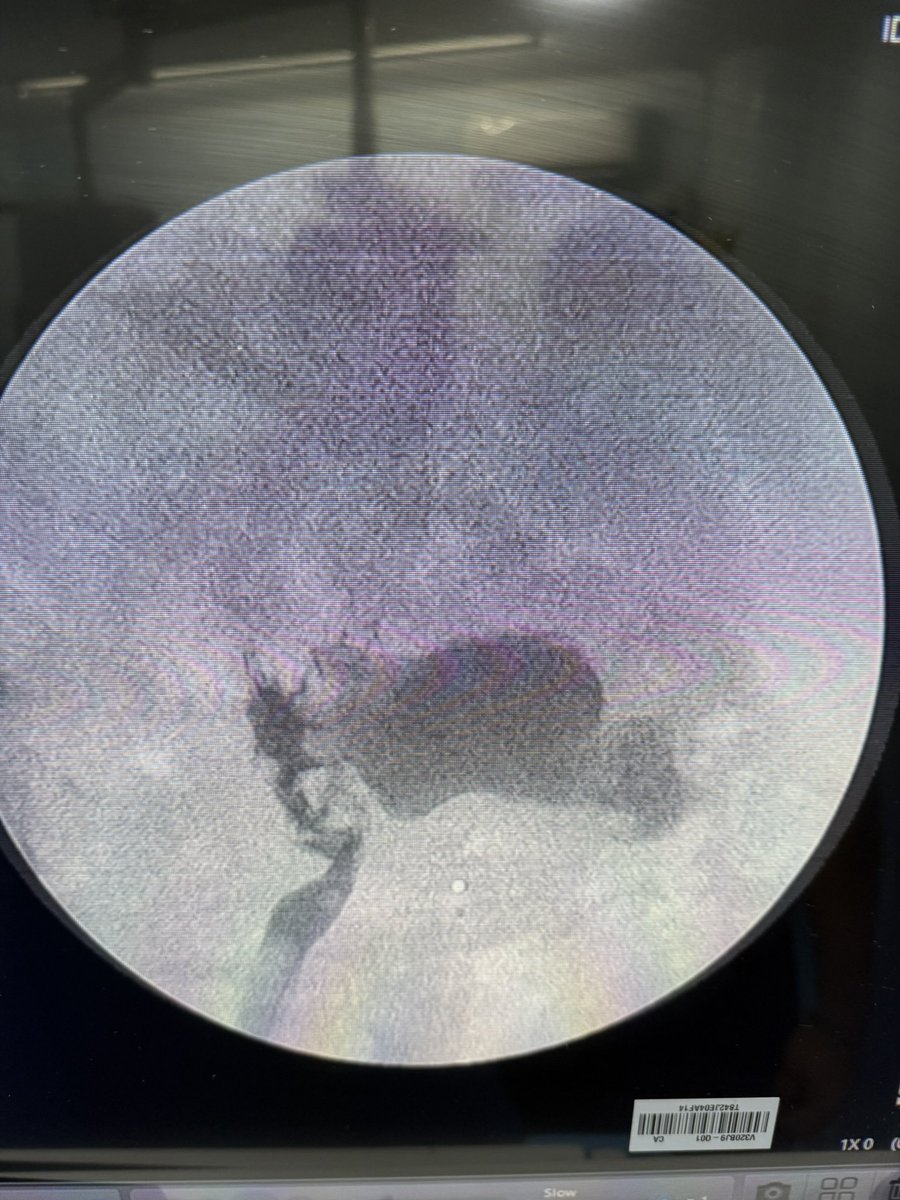

💥 Our Hands-On Course on Ultrasound-Guided PCNL at @CMUN_Urologia was a great success!

An incredible day of practical learning, experience sharing, and passion for advancing minimally invasive surgery